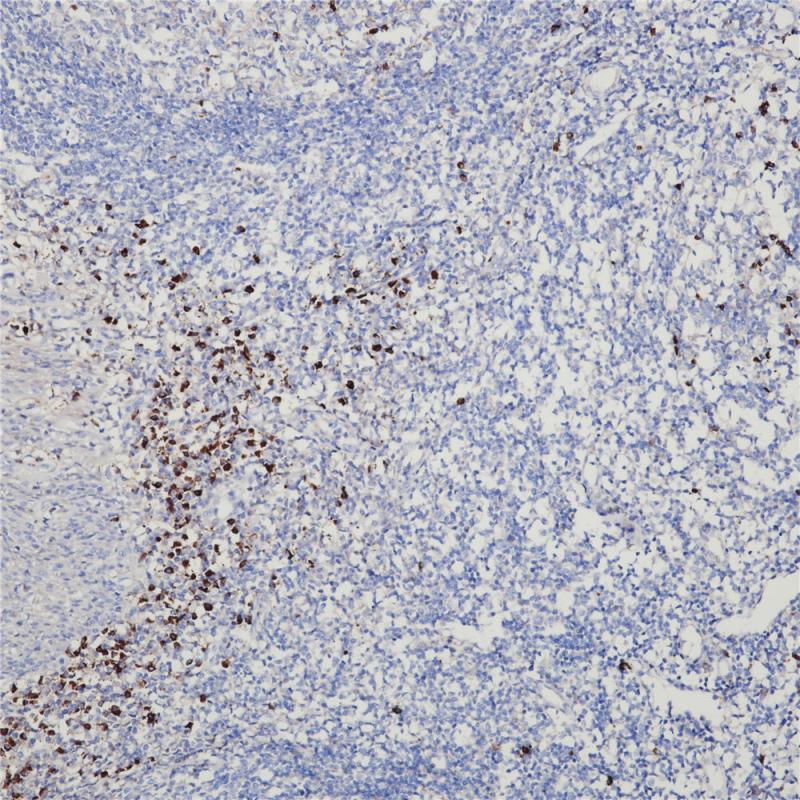

细胞角蛋白5&6在正常组织中主要表达于鳞状上皮、导管上皮基底细胞、肌上皮细胞和间皮细胞,腺上皮表达阴性。该抗体主要用于鳞癌与腺癌、间皮瘤与腺癌的鉴别诊断,也可用于导管上皮良恶性增生的鉴别。

阳性对照

宫颈